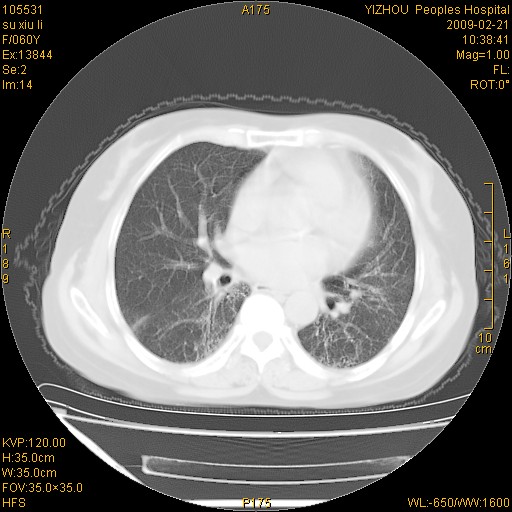

标题: CT18259:两肺间质纤维化?

女,60岁,反复咳嗽1月。

两肺支扩,以肺为著合并双肺较广范纤维化病变。建议除外结核等病变。

两下肺支扩

符合间质感染,部分纤维化表现

特发性间质纤维化

特发性间质纤维化伴支扩!